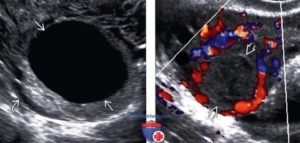

На УЗИ желтое тело определяется как округлое неоднородное образование.

Его видно и при методике исследования через брюшную стенку (трансабдоминальная методика УЗИ), но более достоверные результаты диагностики получают при трансвагинальном методе с использованием внутривагинального датчика.

Как выглядит желтое тело на УЗИ?

- Неправильной формы, с толстым краем и даже валиком.

- С неровным «фестончатым» краем.

- Находится в яичнике на месте бывшего фолликула. Иногда частично представляет собой сгусток крови, образовавшийся после разрыва фолликула.

- Внутренняя его структура на УЗИ крайне разнообразна, может включать кистозные полости и даже кровоизлияния.

- Кровоток при ЦДК по периферии очень активный. Это неудивительно, ведь временный орган должен хорошо кровоснабжаться для нормальной его работы.